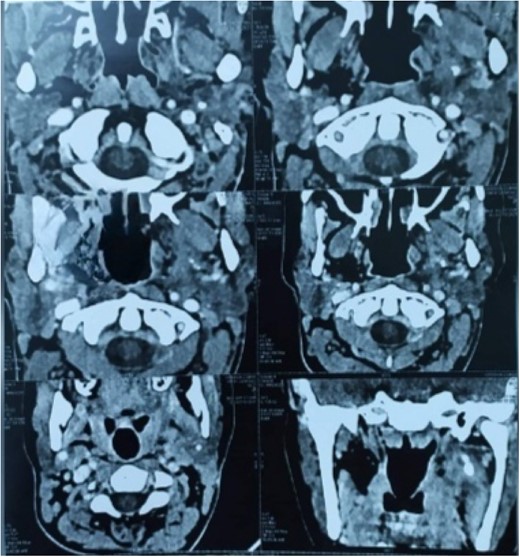

CT-scan has shown well-circumscribed, large-mass heterogenous areas of enhancement with size 6 × 44× 5 cm in the left parapharyngeal space displacing submandibular gland superiorly, carotid sheath anterolateral compressing the oropharyngeal airway (Fig. 1) Routine blood investigations were within the normal limit; hence, surgical removal under general anesthesia decision was done.